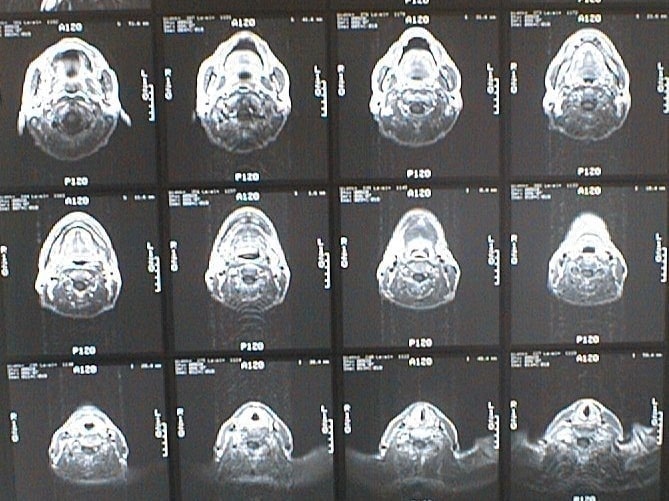

末期がん宣告時と末期がん消滅時の診断画像比較

ここでは、末期がんと宣告された時のCT&MRI画像と、その約3か月後の末期がん消滅時の画像を比較して頂けます。(写真左が「末期がん宣告時の画像」、写真右が「末期がん消滅後の画像」)

MRI画像比較